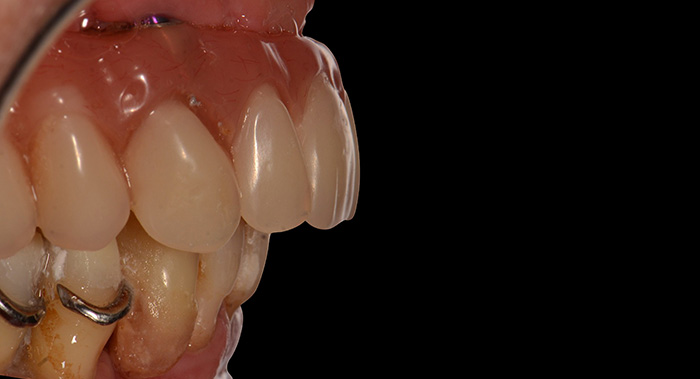

Fig. 16 : Vue de profil

Fig. 17 : Aspect esthétique